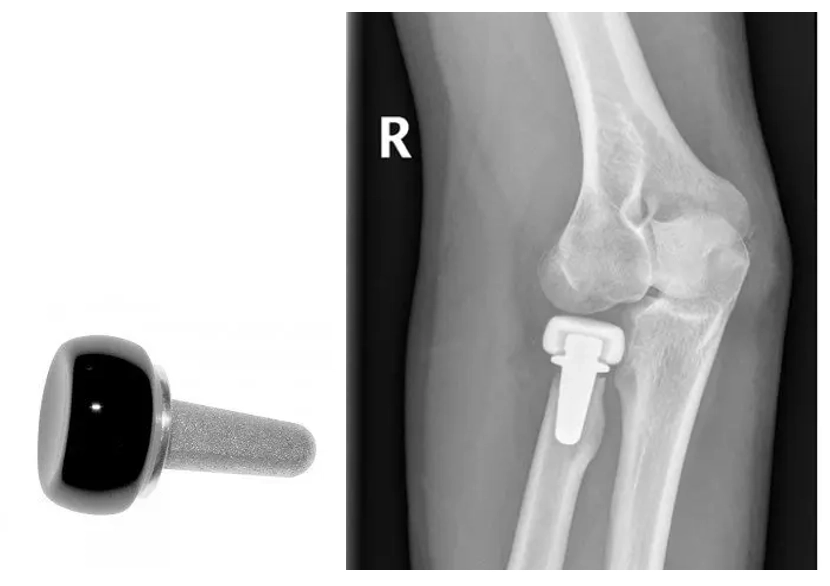

Radial Head Replacement